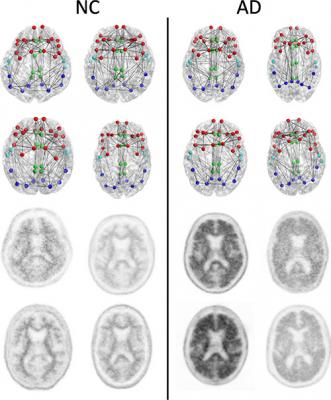

For this study, researchers looked at the brain's structural connectome, a map of white matter tracts that carry signals between different areas of the brain, which provides a way to characterize and measure these connections and how they change through disease or age.

Results from 102 patients enrolled in a national study called the Alzheimer's Disease Neuroimaging Initiative (ADNI) 2 were analyzed. The patients had undergone diffusion tensor imaging (DTI), an MRI method that assesses the integrity of white matter tracts in the brain by measuring how easy it is for water to move along them.

The researchers correlated changes in the structural connectome with results from florbetapir positron emission tomography (PET) imaging, a technique that measures the amount of beta amyloid plaque in the brain. Increased florbetapir uptake corresponds with greater amounts of the protein.

The results showed a strong association between florbetapir uptake and decreases in strength of the structural connectome in each of the five areas of the brain studied.